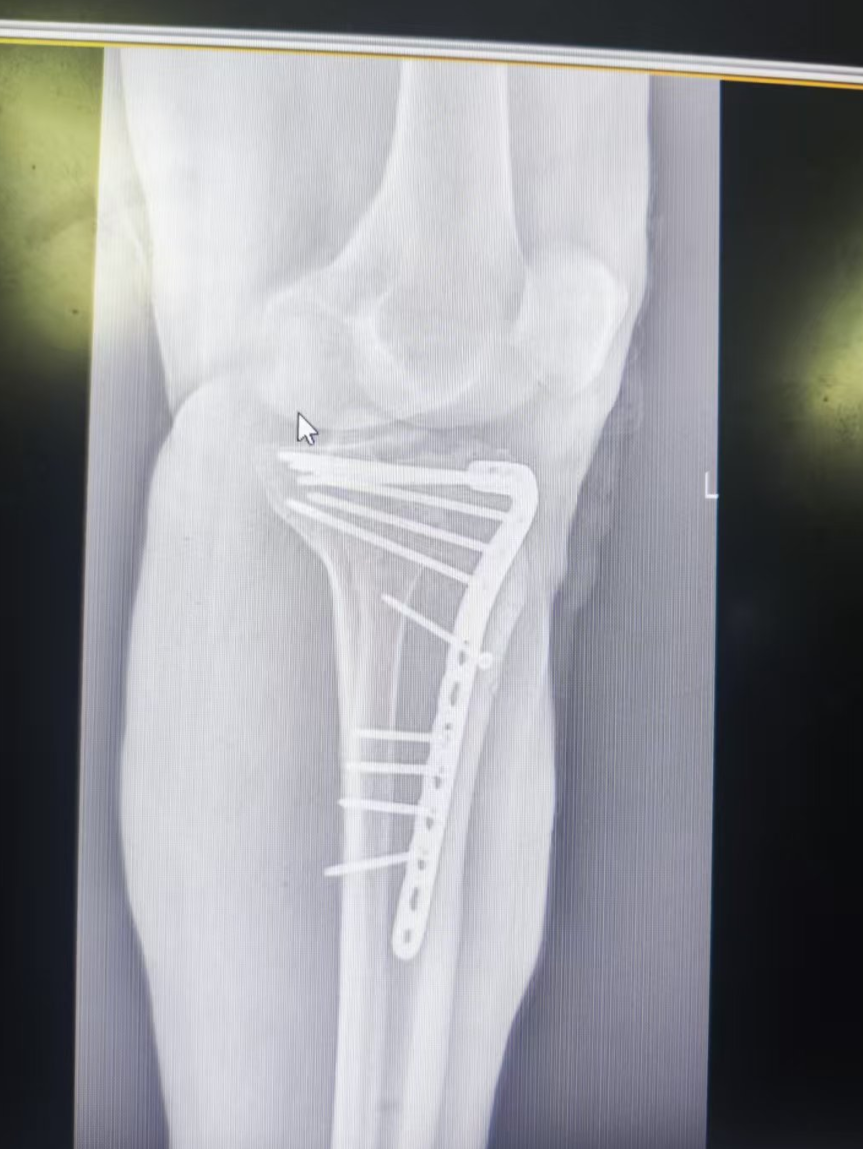

患者因严重外伤入院,被诊断为锁骨骨折、肋骨骨折以及胫骨平台骨折。

手术当日,骨科与胸外科团队紧密配合,凭借精湛的医术和丰富的经验,克服了手术中的重重困难。在麻醉科的全力保障下,手术顺利进行,成功为患者完成了锁骨、肋骨及胫骨平台骨折内固定手术。此次手术的成功,充分展示了医院多学科协作的强大实力和救治复杂病例的高超水平。